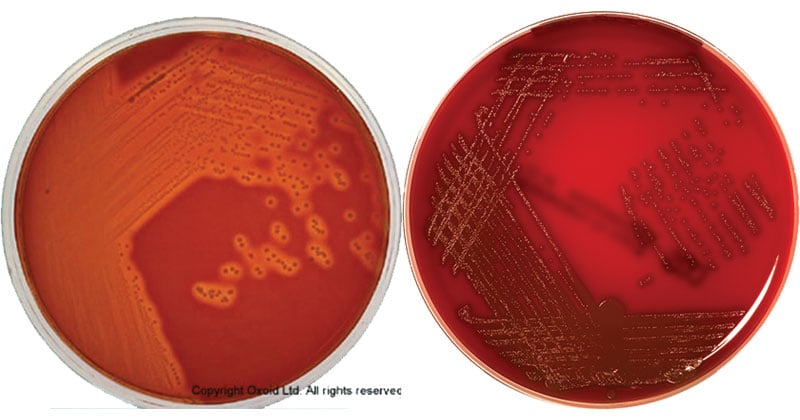

Кампилобактер фетус: патогенез и инфекции